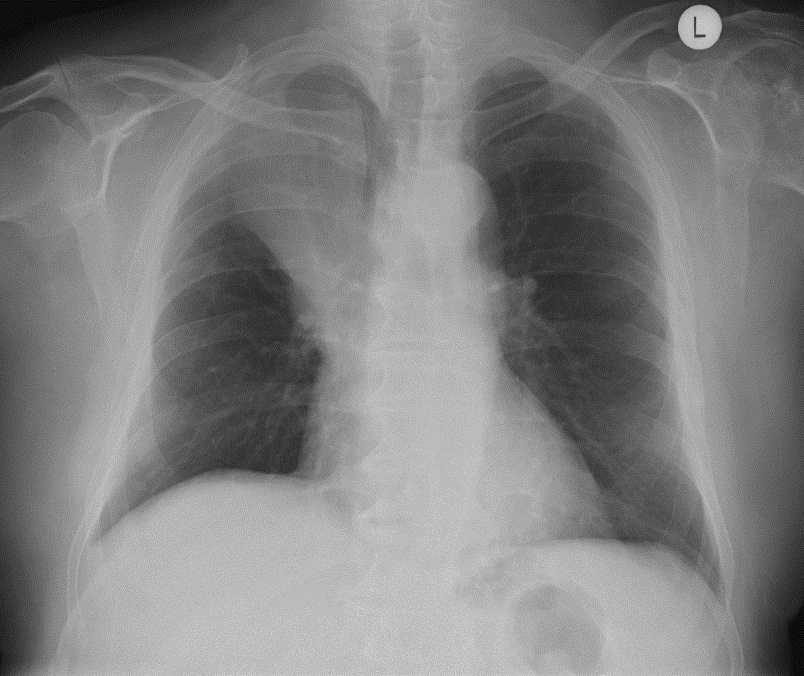

Left lower lobe atelectasis

The heart slightly rotates and the left hilum is pulled down. The flat waist sign describes the flattenin of the left heart border as a result of downward shift of hilar structures and resultant cardiac rotation.